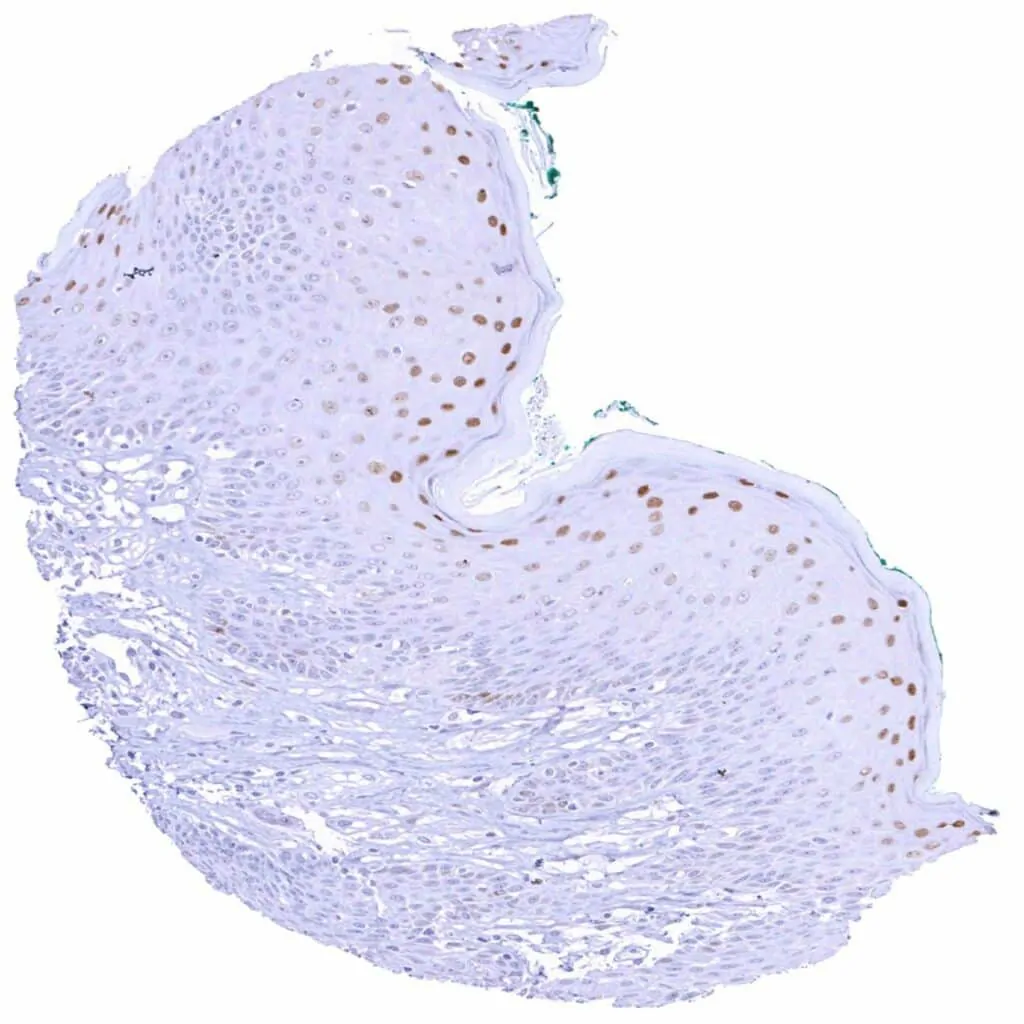

Kidney, pelvis, urothelium – Weak to strong Cyclin E1 staining of urothelial cells is limited to the top cell layers of the urothelium. The staining intensity increases towards the surface